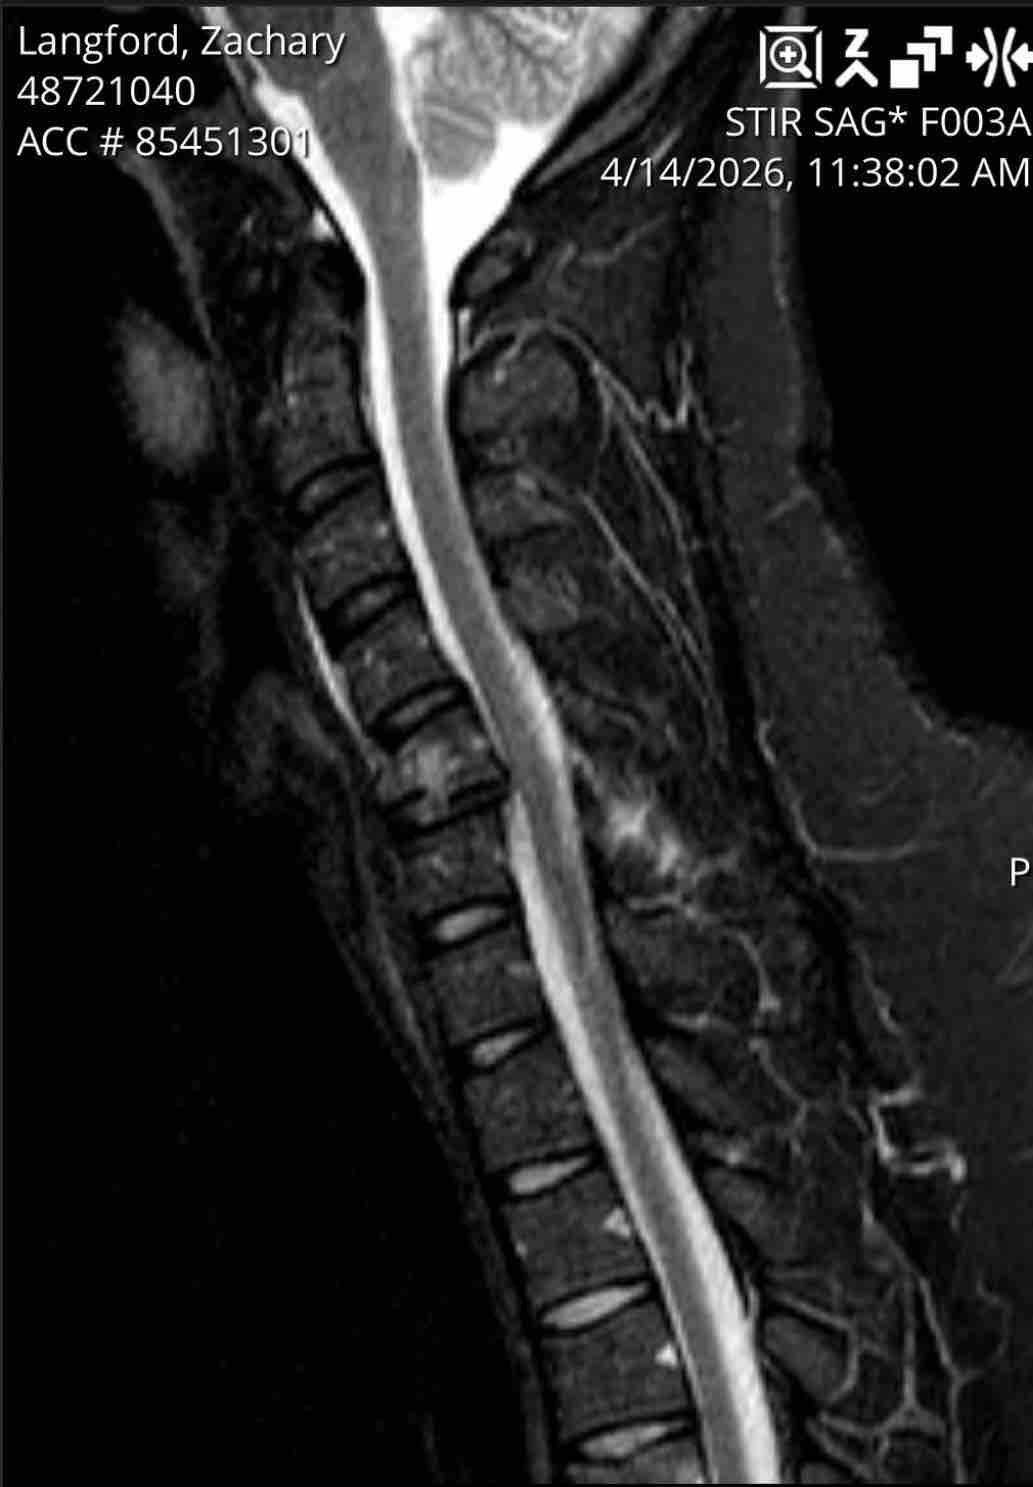

Zach was thrown into the back of the ambulance during the crash and suffered severe injuries.

He was airlifted from the scene by Erlanger LifeForce and transported to Vanderbilt University Medical Center, where he underwent extensive evaluation. Zach has been diagnosed with a fractured neck and is scheduled to undergo major surgery on the morning of April 15, 2026.